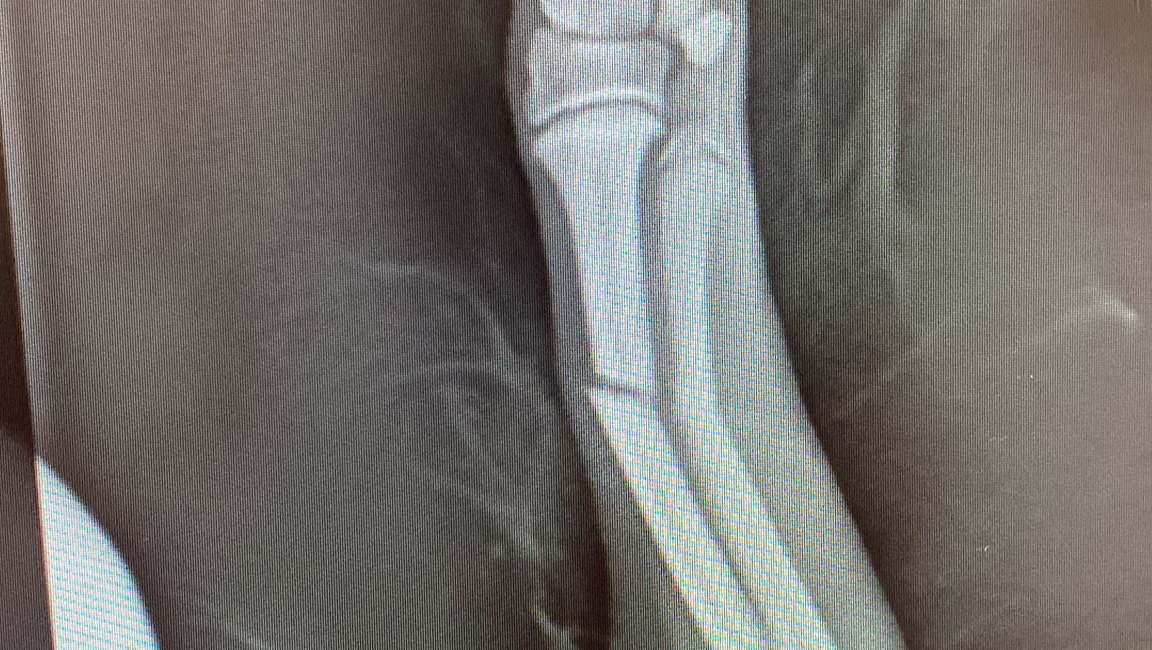

Little snoop dog arrived, he is just a young 12 week old puppy who is loving life in foster with some of his friends. Snoop had an unfortunate accident after jumping from a small box holding his toys. A freak accident or his bones are just not strong enough at the moment - we don't know.

What we do know is, we rushed him straight in to our vets and he had surgery the very same afternoon.

Snoop is now sporting an External Fixator and is having regular checks with the vets to ensure all is going well. We have also added supplements to his diet to strengthen his bones and aid his recovery.